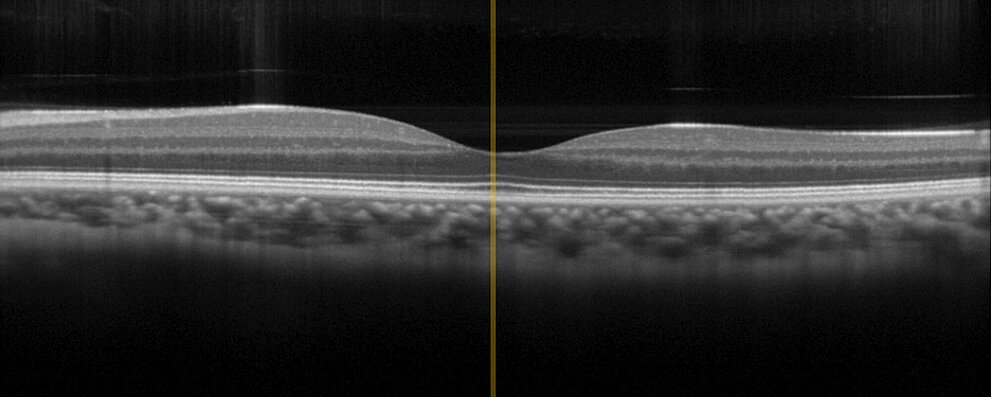

Endoscopy and in vivo diagnostics are among the most sophisticated medical technologies since they are applied within or on the living organism. The highest reliability is indispensable here. PI's decades of experience as a supplier to companies in medical technology and the 30 years of experience as a manufacturer of piezo components are essential assets that PI contributes in the development and manufacture of assemblies and subsystems. For example, PI offers more than just one drive for variable focusing of chip-on-the-tip endoscopes. And for optical coherence tomography (OCT) with its applications in ophthalmology or dermatology, PI offers different drive technologies that can be adapted to device-specific requirements, such as size or travel range, for a precise positioning of the optics.